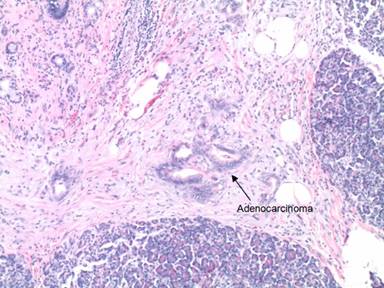

Evaluation with an abdominal ultrasound showed a questionable mass in the head of the pancreas. A CT scan revealed a 2.9 cm soft tissue mass in the head of the pancreas and uncinate process with associated pancreatic ductal and adjacent biliary ductal dilatation (Figure 2). A Whipple procedure was performed and pathology was consistent with a poorly differentiated exocrine adenocarcinoma of the pancreatic head (Figure 3) with invasion into the common bile duct and metastases to two of eight peripancreatic lymph nodes (stage T3N1M0). The patient underwent adjuvant radiation therapy along with capecitabine followed by weekly gemcitabine, with a plan to complete a total of six months of adjuvant chemotherapy. However, a restaging CT of the abdomen and pelvis two months later showed studding along the greater omentum and mesentery, which was concerning for early peritoneal spread of the tumor. A PET/CT revealed intensely increased metabolic activity in the gallbladder fossa measuring 5.8x3.4 cm with a maximum standardized uptake value (SUVm) of 10.3. There was an additional focus of intensely increased metabolic uptake near the left anterior abdominal wall with a maximum SUVm of 5.8. Due to obvious metastatic disease, he was started on systemic chemotherapy with folinic acid (leucovorin), 5-fluorouracil, irinotecan and oxaliplatin (FOLFIRINOX). Two months later, a restaging PET/CT showed a new 3 cm metastasis in the right lobe of the liver. The patient’s condition deteriorated rapidly; he developed sepsis secondary to cholangitis and was admitted to the intensive care unit. A family decision was ultimately made to focus on comfort-oriented care, and he expired soon thereafter.

Figure 3. Microphotograph displaying adenocarcinoma (arrow) of the pancreas (H&E, 4x magnification). |